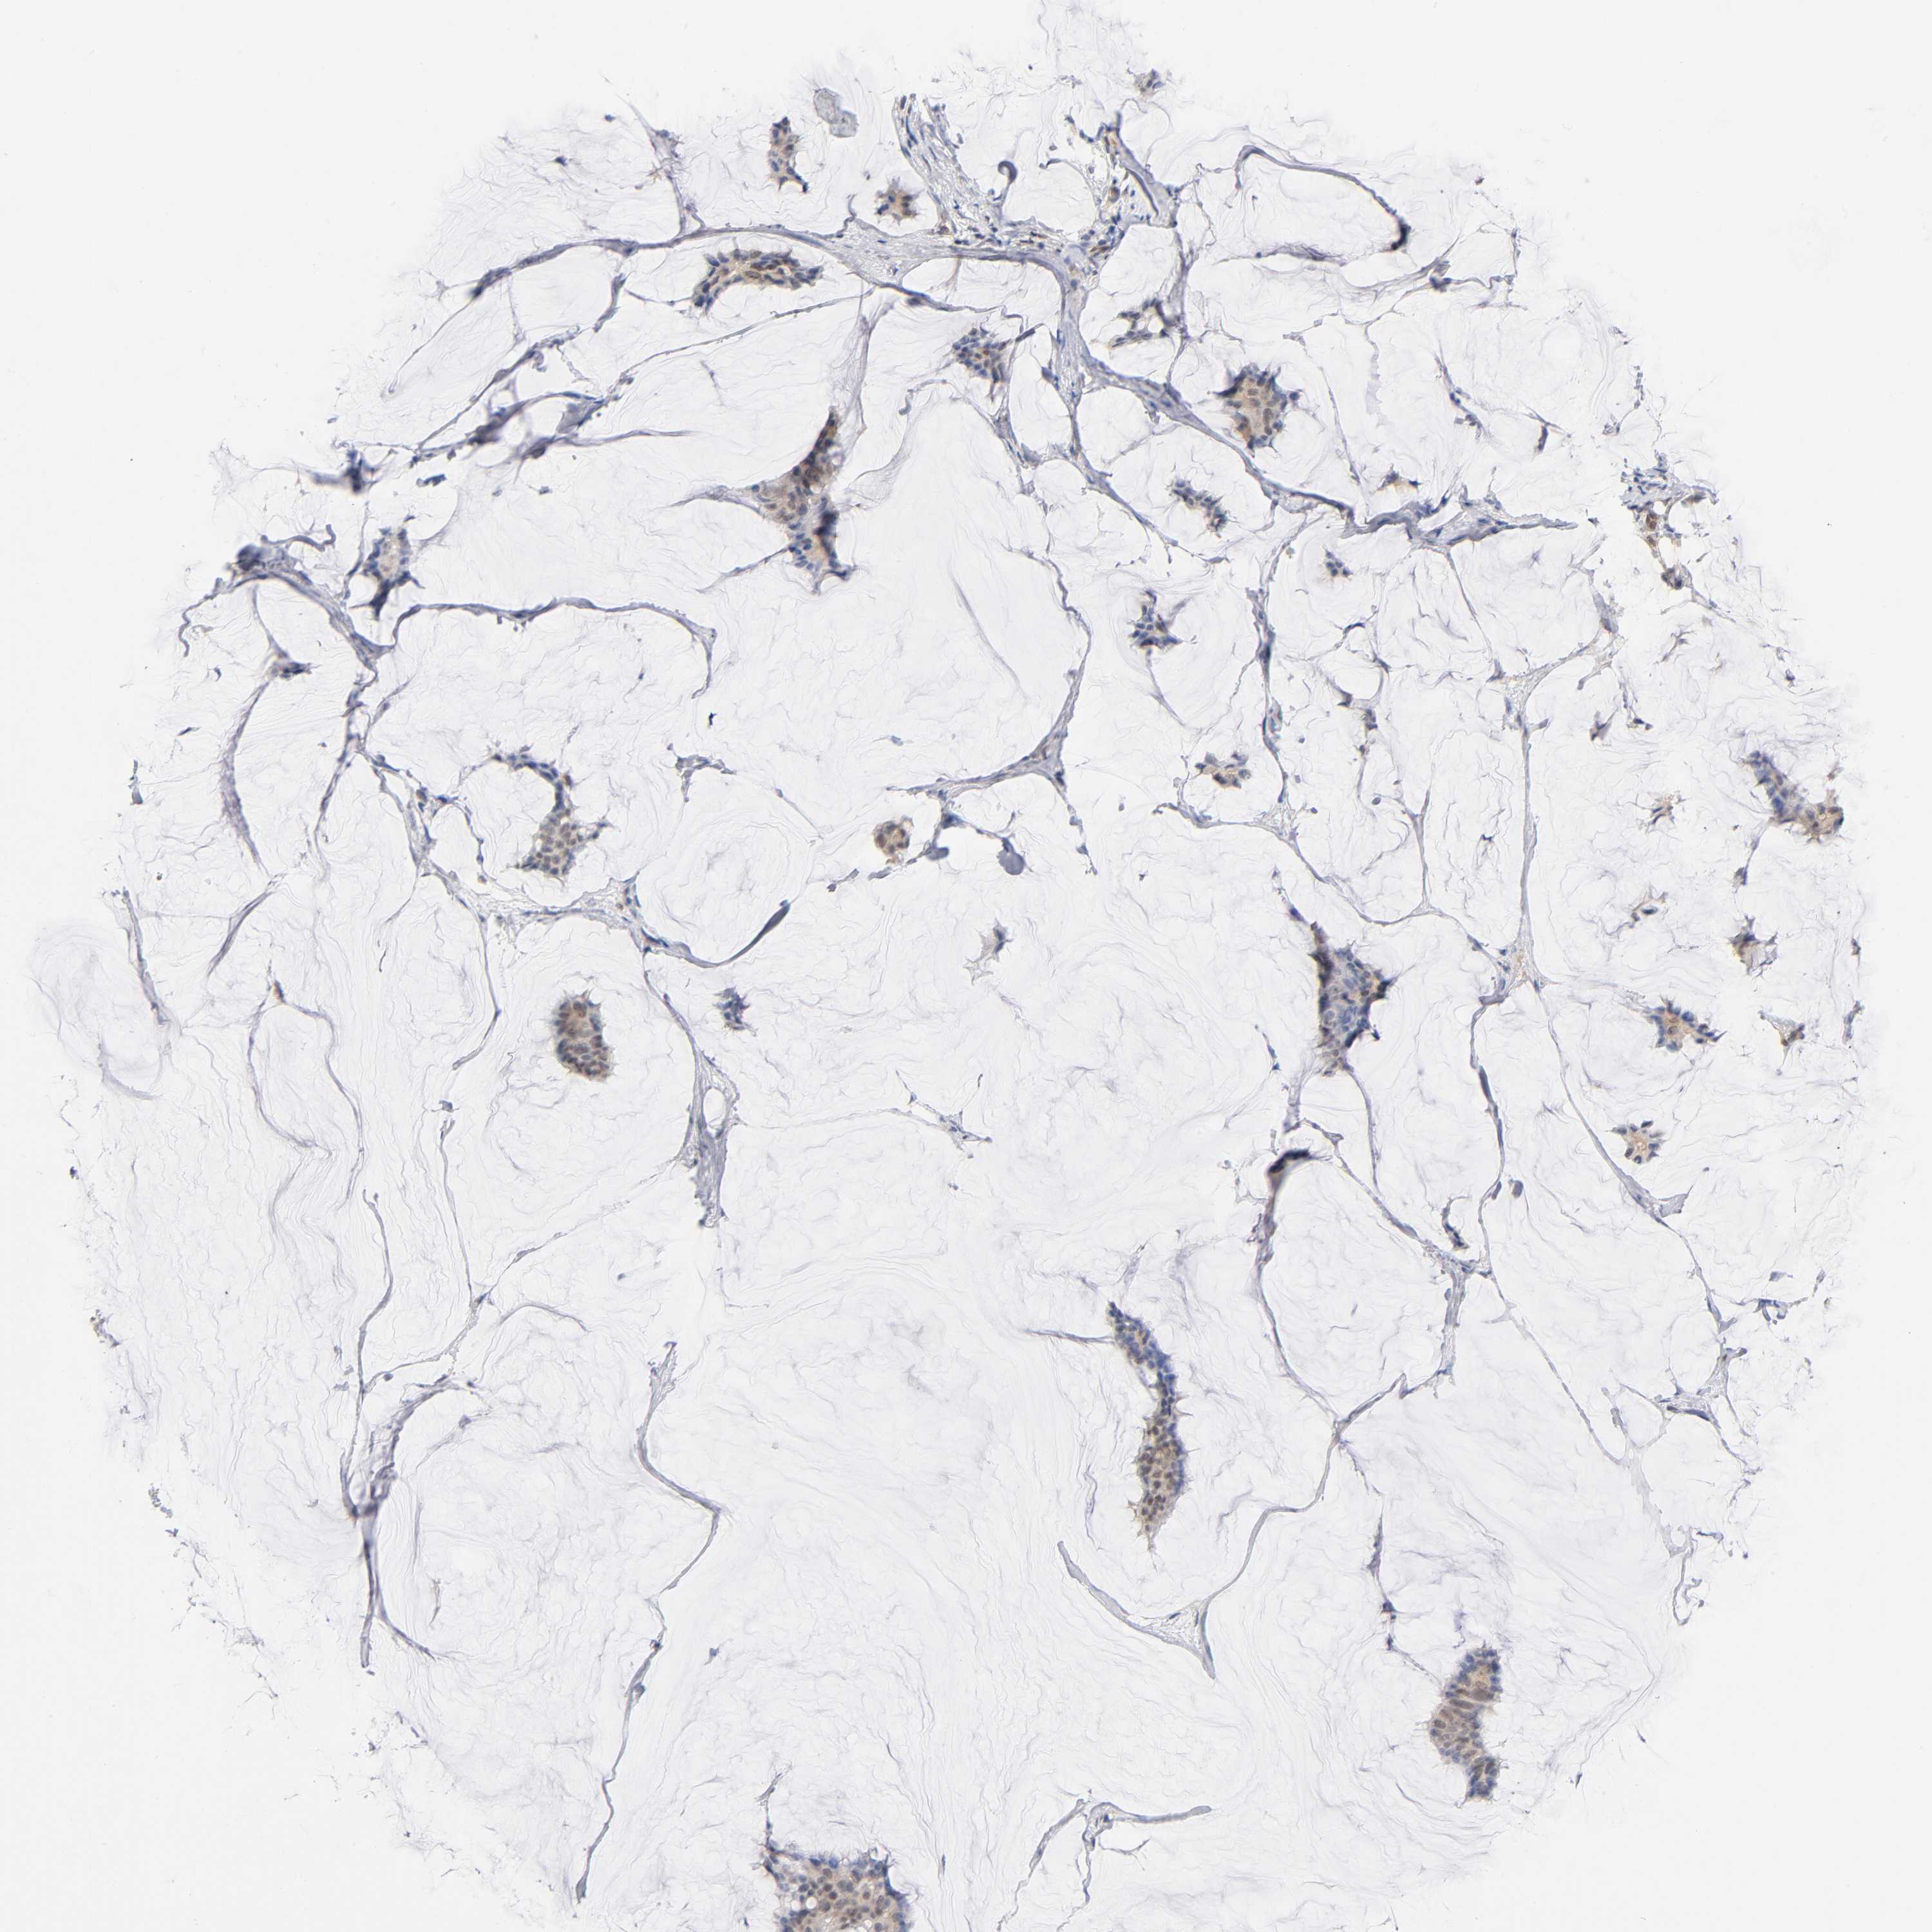

BRCA TCGA BRCA VALIDATION PROTEIN EXPRESSION